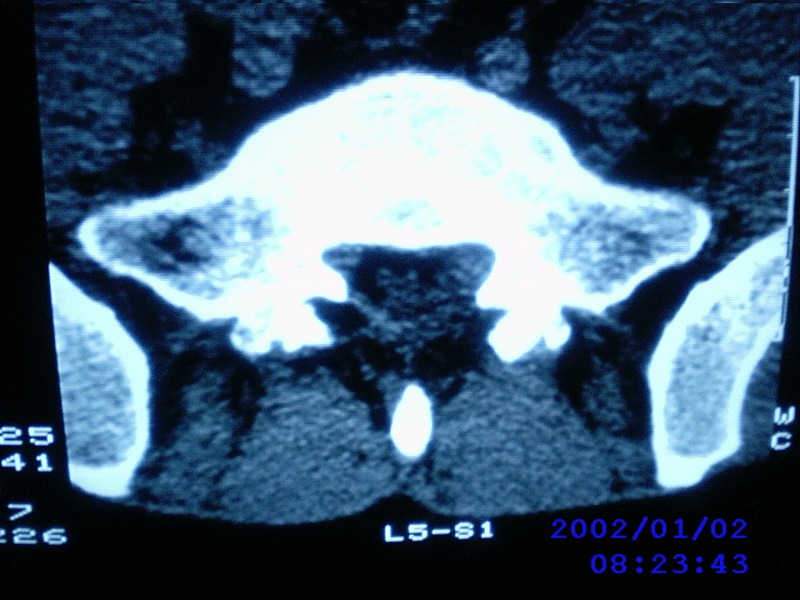

患者,男性,40岁,腰痛伴左下肢疼痛、麻木6年。5年前做过腰椎间盘手术,具体是哪个位置病人记不清了。

我拍的是l4-5、l5-s1

1)l4/5及l5/s1左侧椎板术后改变。2)l5/s1椎间盘突出,l5椎体下缘许莫氏结节。3)l4/5椎间盘膨出并突出。4)l3/4椎间盘膨出。

1)l4/5及l5/s1左侧椎板术后改变。2)l5/s1椎间盘突出,l5椎体下缘许莫氏结节。3)l4/5椎间盘膨出并突出。

1)l4/5及l5/s1左侧椎板术后改变。2)l5/s1椎间盘突出,l5椎体下缘许莫氏结节。3)l4/5椎间盘膨出并突出。4)l3/4椎间盘膨出。支持!